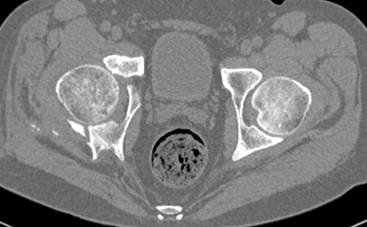

Интересно было бы посмотреть рентгенограммы до операции. У меня впечатление, что я не все вижу, что тут есть... Уважаемые Господа "тазисты" и "тазологи", к какому типу переломов вертлужной впадины по Летурнелю вы бы отнесли это случай?

Из переломов проходящих через крыло и/или заднюю стенку ни простой перелом "передней колонны" (явно имеется пером задней стенки, и не видно перелома седалищной или лонной), ни простой "поперечный", ни ассоциированный "Т-образный" (т.к есть перелом крыла и не видно перелома седалишной), ни ассоциированный "задняя колонна+задняя стенка", на ассоциированный "поперечный+задняя стенка", ни ассоциированный "передняя колонна+задняя гемисфера" (не видно перелома седалищной), ни ассоциированный "обе колонны" (не видно перелома лонной седалищной) не подходят под эту классификацию....

к таковым себя не причисляю, но...обычное дело для нашей страны - выкладывать 3D и не показывать стандартные проекции Judet. Дигност представляет те ракурсы, которые по-его мнению наиболее информативны, более того комп сам достраивает какие-то мелкие повреждения по 3D по своему усмотрению. По данной реконструкции можно предполагать высокий двухколонный перелом с оскольчатыми передней и задней колоннами, оскольчатую высокую переднюю колонну с задним полупоперечником или одно из перечисленных с вовлечение КПС. У меня впечатление за второй вариант, но нужно обследовать нормально - проекции, сканы.

высылаю дополнительно сканы.

итак, второй вариант: высокий двухколонный с вовлечением КПС... Ни одно из основных повреждений не репонировано, кроме задней стенки. Скорее всего попытка реконструкции вертлуги сейчас будет очень травматичной и не очень эфективной, т.е. вероятный риск более значим, чем ожидаемая польза... Лучше подождать, и потом сразу эндопротез